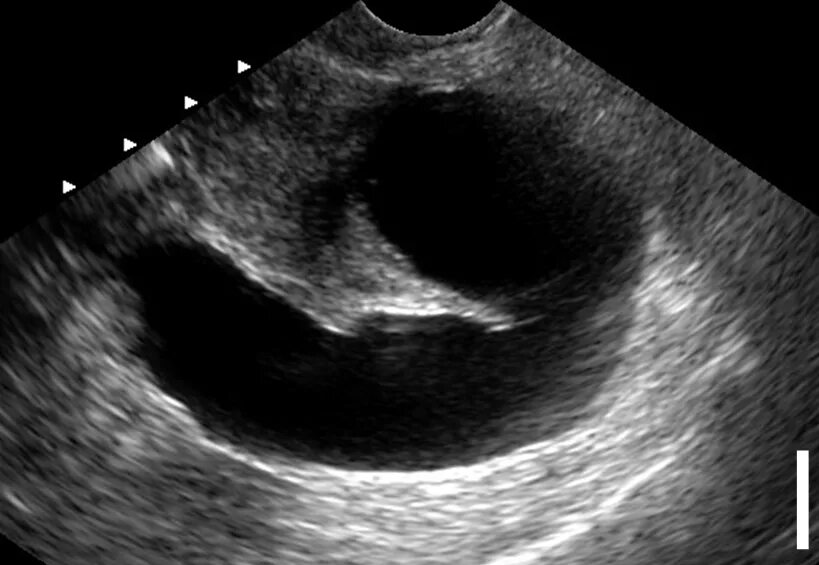

Гидросальпинкс что это такое как лечить